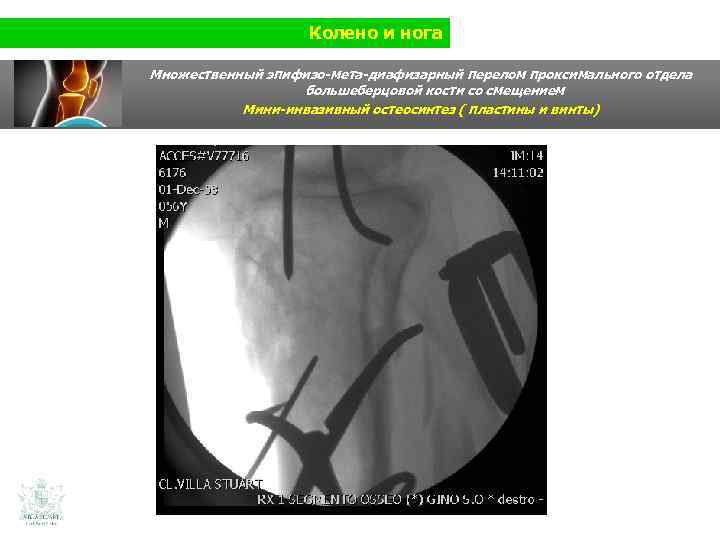

Колено и нога Множественный эпифизо-мета-диафизарный перелом проксимального отдела большеберцовой кости со смещением (Shatzer 6) Мини-инвазивный остеосинтез ( пластины и винты)

Колено и нога Множественный эпифизо-мета-диафизарный перелом проксимального отдела большеберцовой кости со смещением Мини-инвазивный остеосинтез ( пластины и винты)